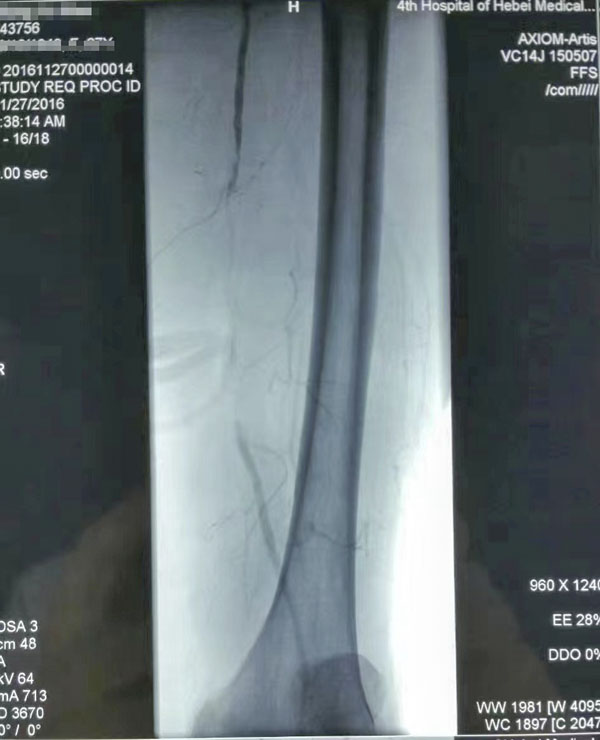

介入治疗前后对比

糖尿病足重在预防,而预防和治疗下肢血管病变是防治糖尿病足的有效措施。下肢血运重建是糖尿病下肢血管病变治疗的根本采用球囊扩张开通狭窄或闭塞的下肢动脉(介入治疗),恢复直达足部的血流,是治疗糖尿病下肢血管病变的根本措施,具有立竿见影的效果这也是近年来在糖尿病足诊治方面取得的又一新进展,为广大糖尿病下肢血管病变患者解除了痛苦使糖尿病足患者截肢率由34%降至4%。世界防治糖尿病日到来之际,希望广大糖尿病患者关注糖尿病下肢血管病变,保护自己的双足,做到早发现、早治疗,提升幸福感快乐每一天。